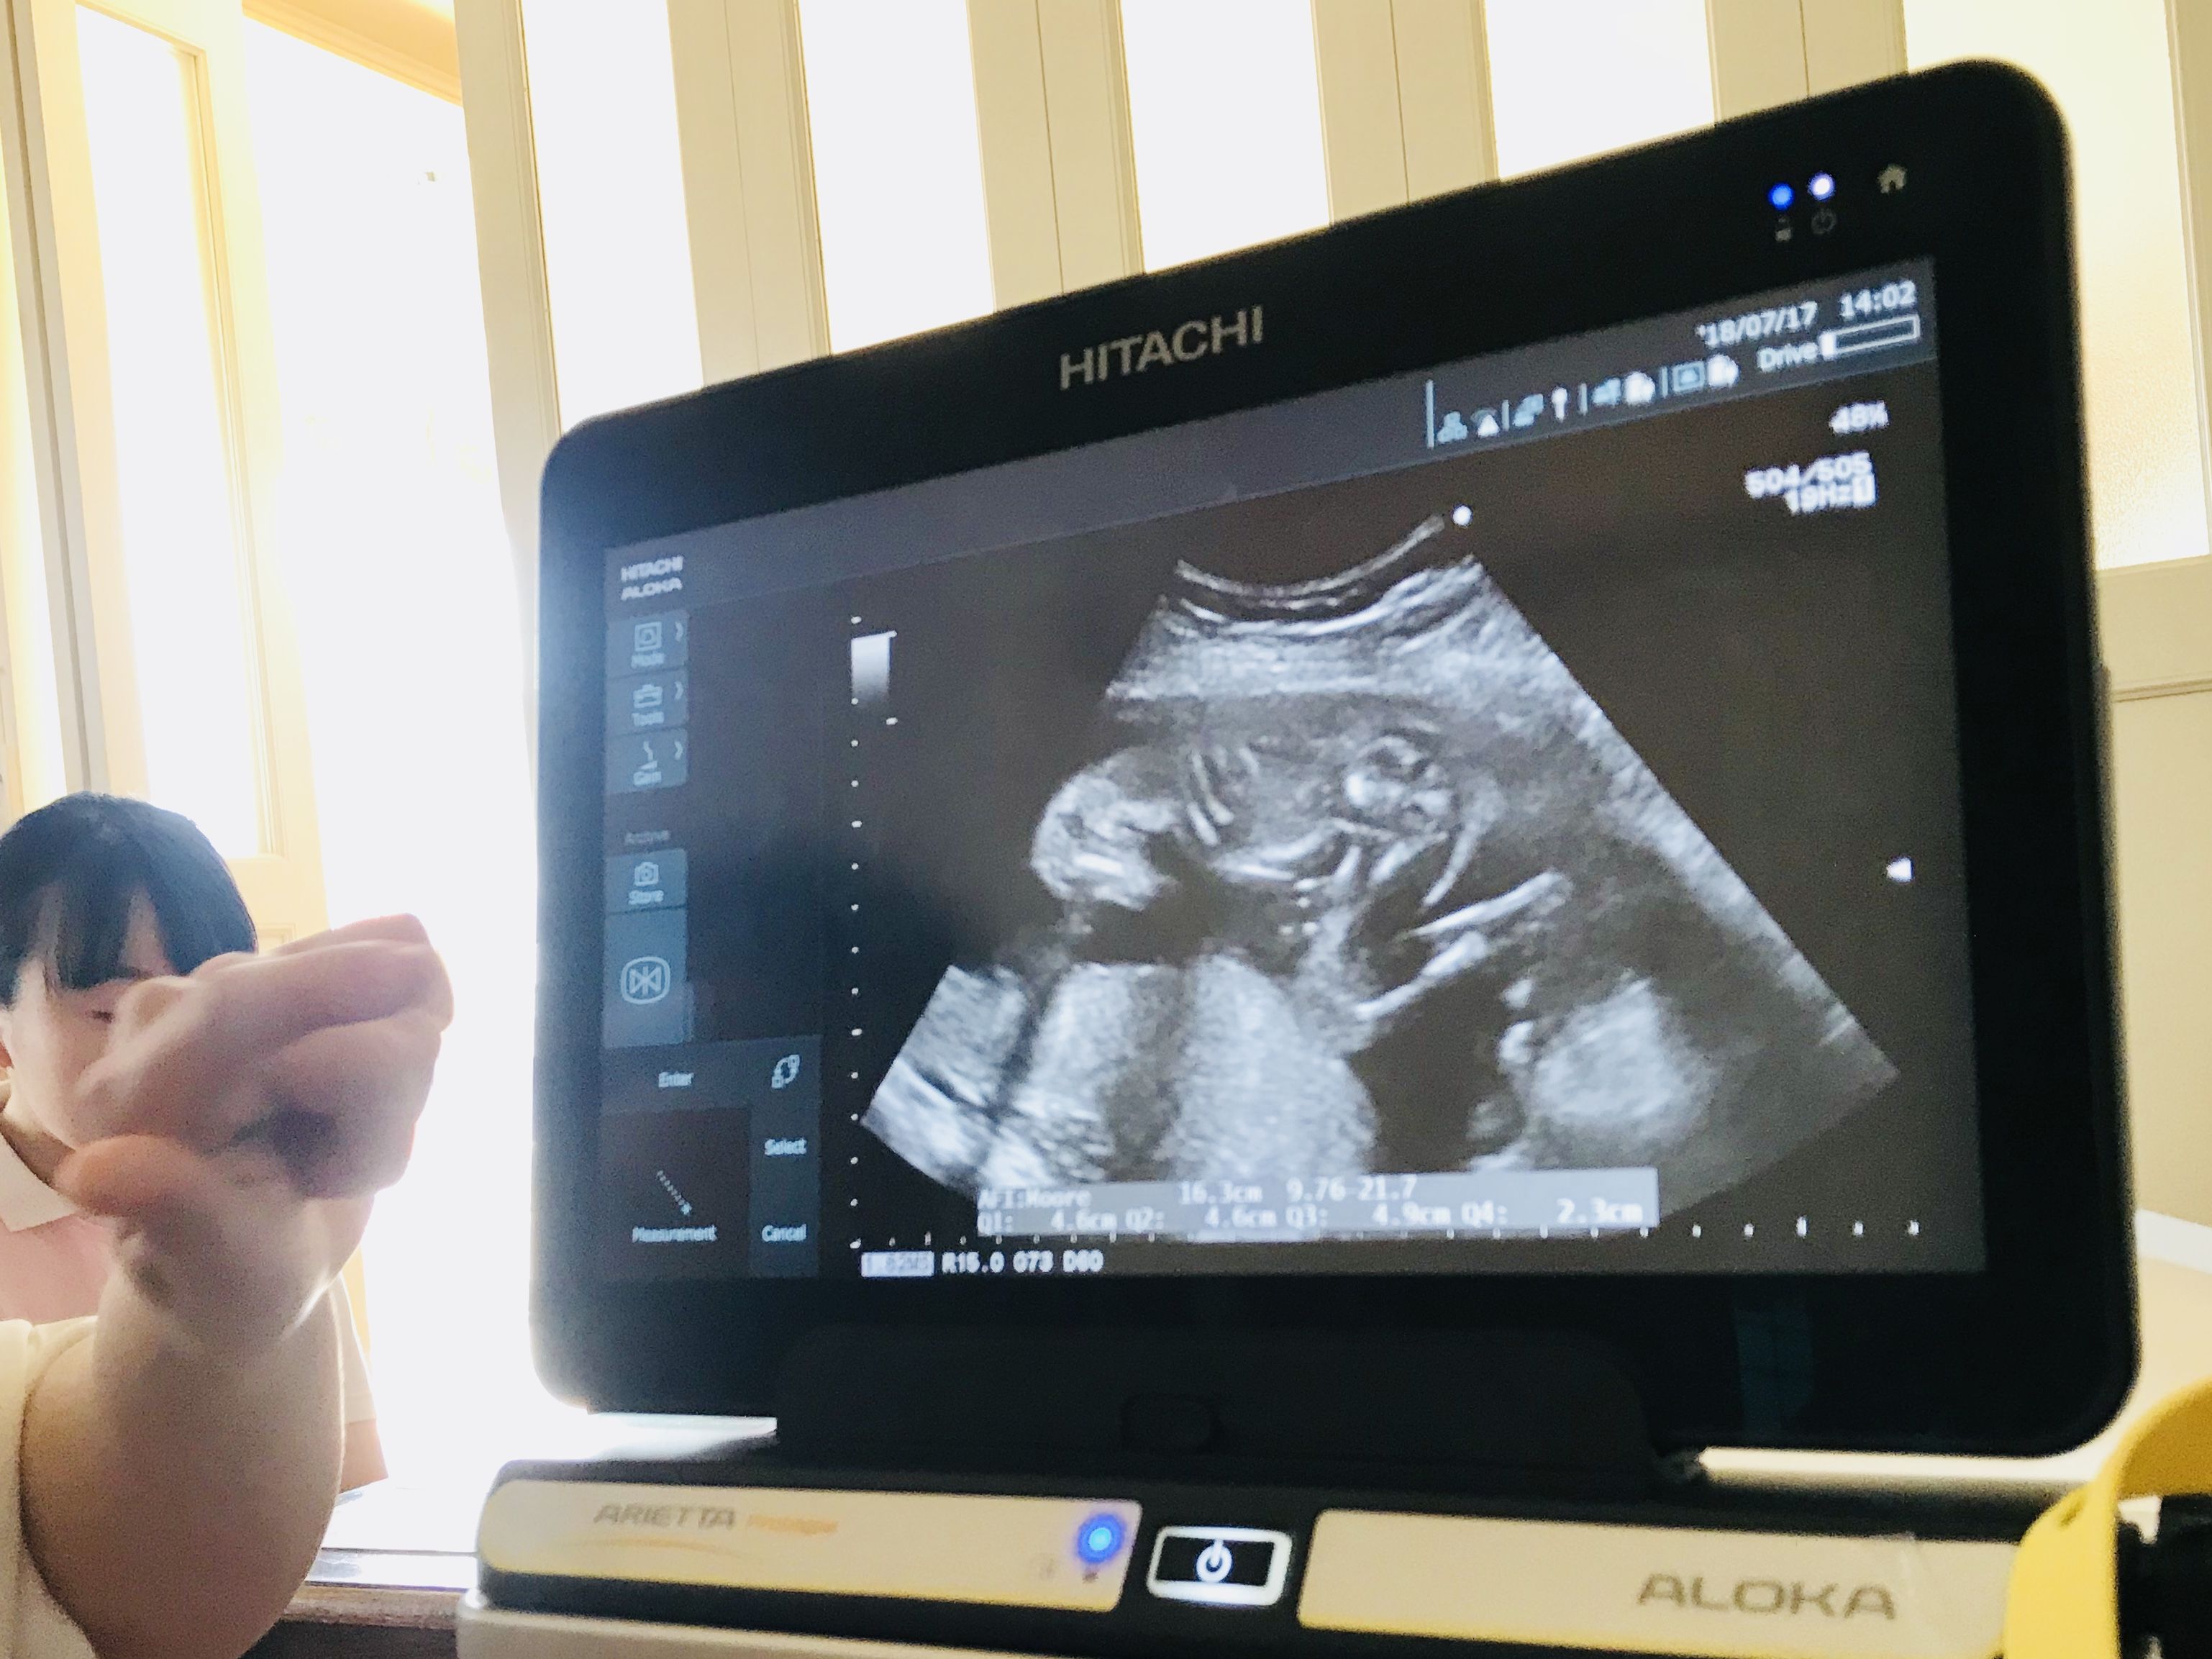

そんな不安を抱えつつ、この間検診に行って超音波エコーを見てもらったら、「赤ちゃんの推定体重は498gでしょう」って言われました。

私は今まで知らなかったんですけど、この間の検診の時に超音波エコーを見ながら先生が

「赤ちゃんの頭の大きさとかお腹周り、太ももの長さを測って、それを複雑な式に当てはめるんですよ〜」

って教えてくれました。